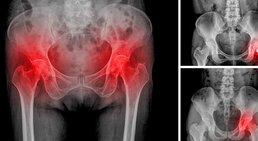

Hüfte

Als Ursache für Hüft- und Leistenschmerzen kommen neben einem geschädigten Hüftgelenk oder Hüftinstabilitäten auch chronische Muskelverspannungen,...